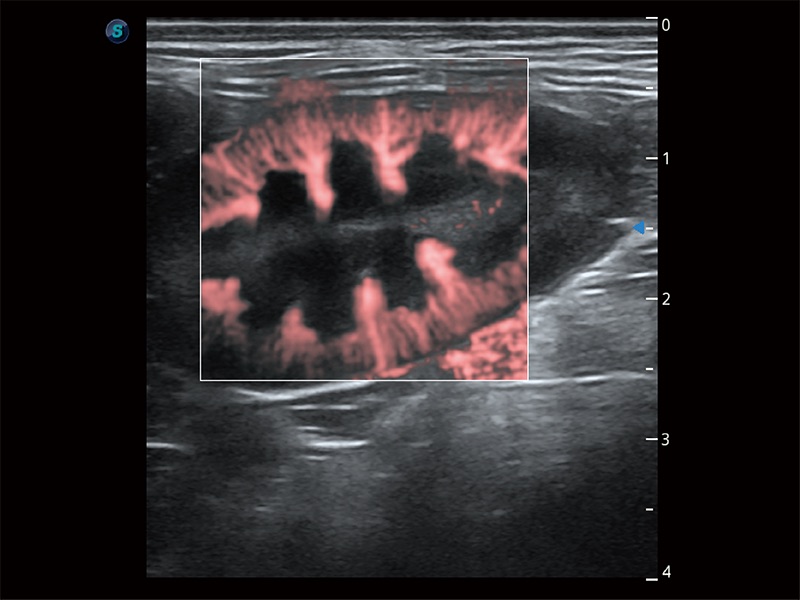

• Micro F 显微血流成像

极大提升超低速微细血流的检出能力,同时更精准地滤除软组织和超声信号,为兽用医生提供以往无法通过常规血流获得的疾病诊断信息。

• Bright Flow 立体血流成像

在传统二维血流成像的基础上,呈现血流的立体感,具有动感的生命力之美。即便是微小的血管也能轻松应对,提高了血流的视觉敏感性。

优异的基础图像

ProPet 80 全新的动物超声智能软件和丰富的探头群,为动物医生提供了高清晰度和精细分辨率的图像,无论在宠物、马科、畜牧还是实验室动物等应用中都可以轻松应对,为您的日常工作带来满意的体验。

(犬)肾脏显微血流